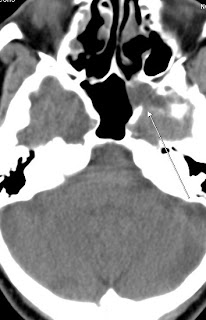

Nontraumatic Skull Base Defect with CSF Rhinorrhea

The sphenoid sinus is a frequent site of spontaneous osteodural defects. Originally described by Cruveilhier in 1877 and Sternberg the lateral craniopharyngeal canal corresponds to a fusion line of the basisphenoid with the greater sphenoid wing. Probably more relevant are aberrant arachnoid granulations, which have penetrated the dura but failed to reach a venous sinus in this location. Accordingly, a smooth lobulated appearance of the defects has been described from an anatomic standpoin as well as by CT and has been designated as "arachnoid pits." The concept of arachnoid granulations as precursors of osteodural defects seems to hold true for the lateral wall of the sphenoid sinus.